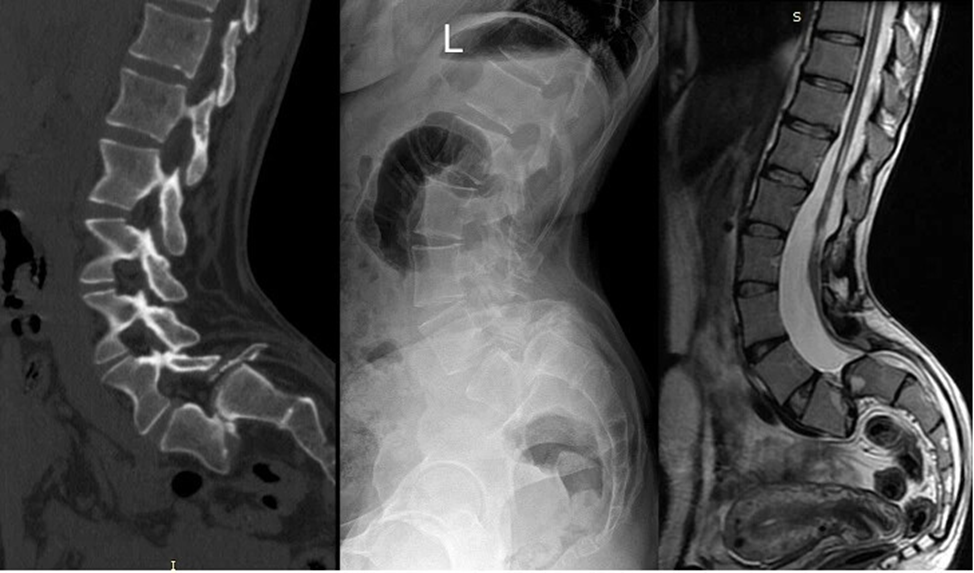

А вот и снимки пациентки. 100% листез! Как не оперировать!